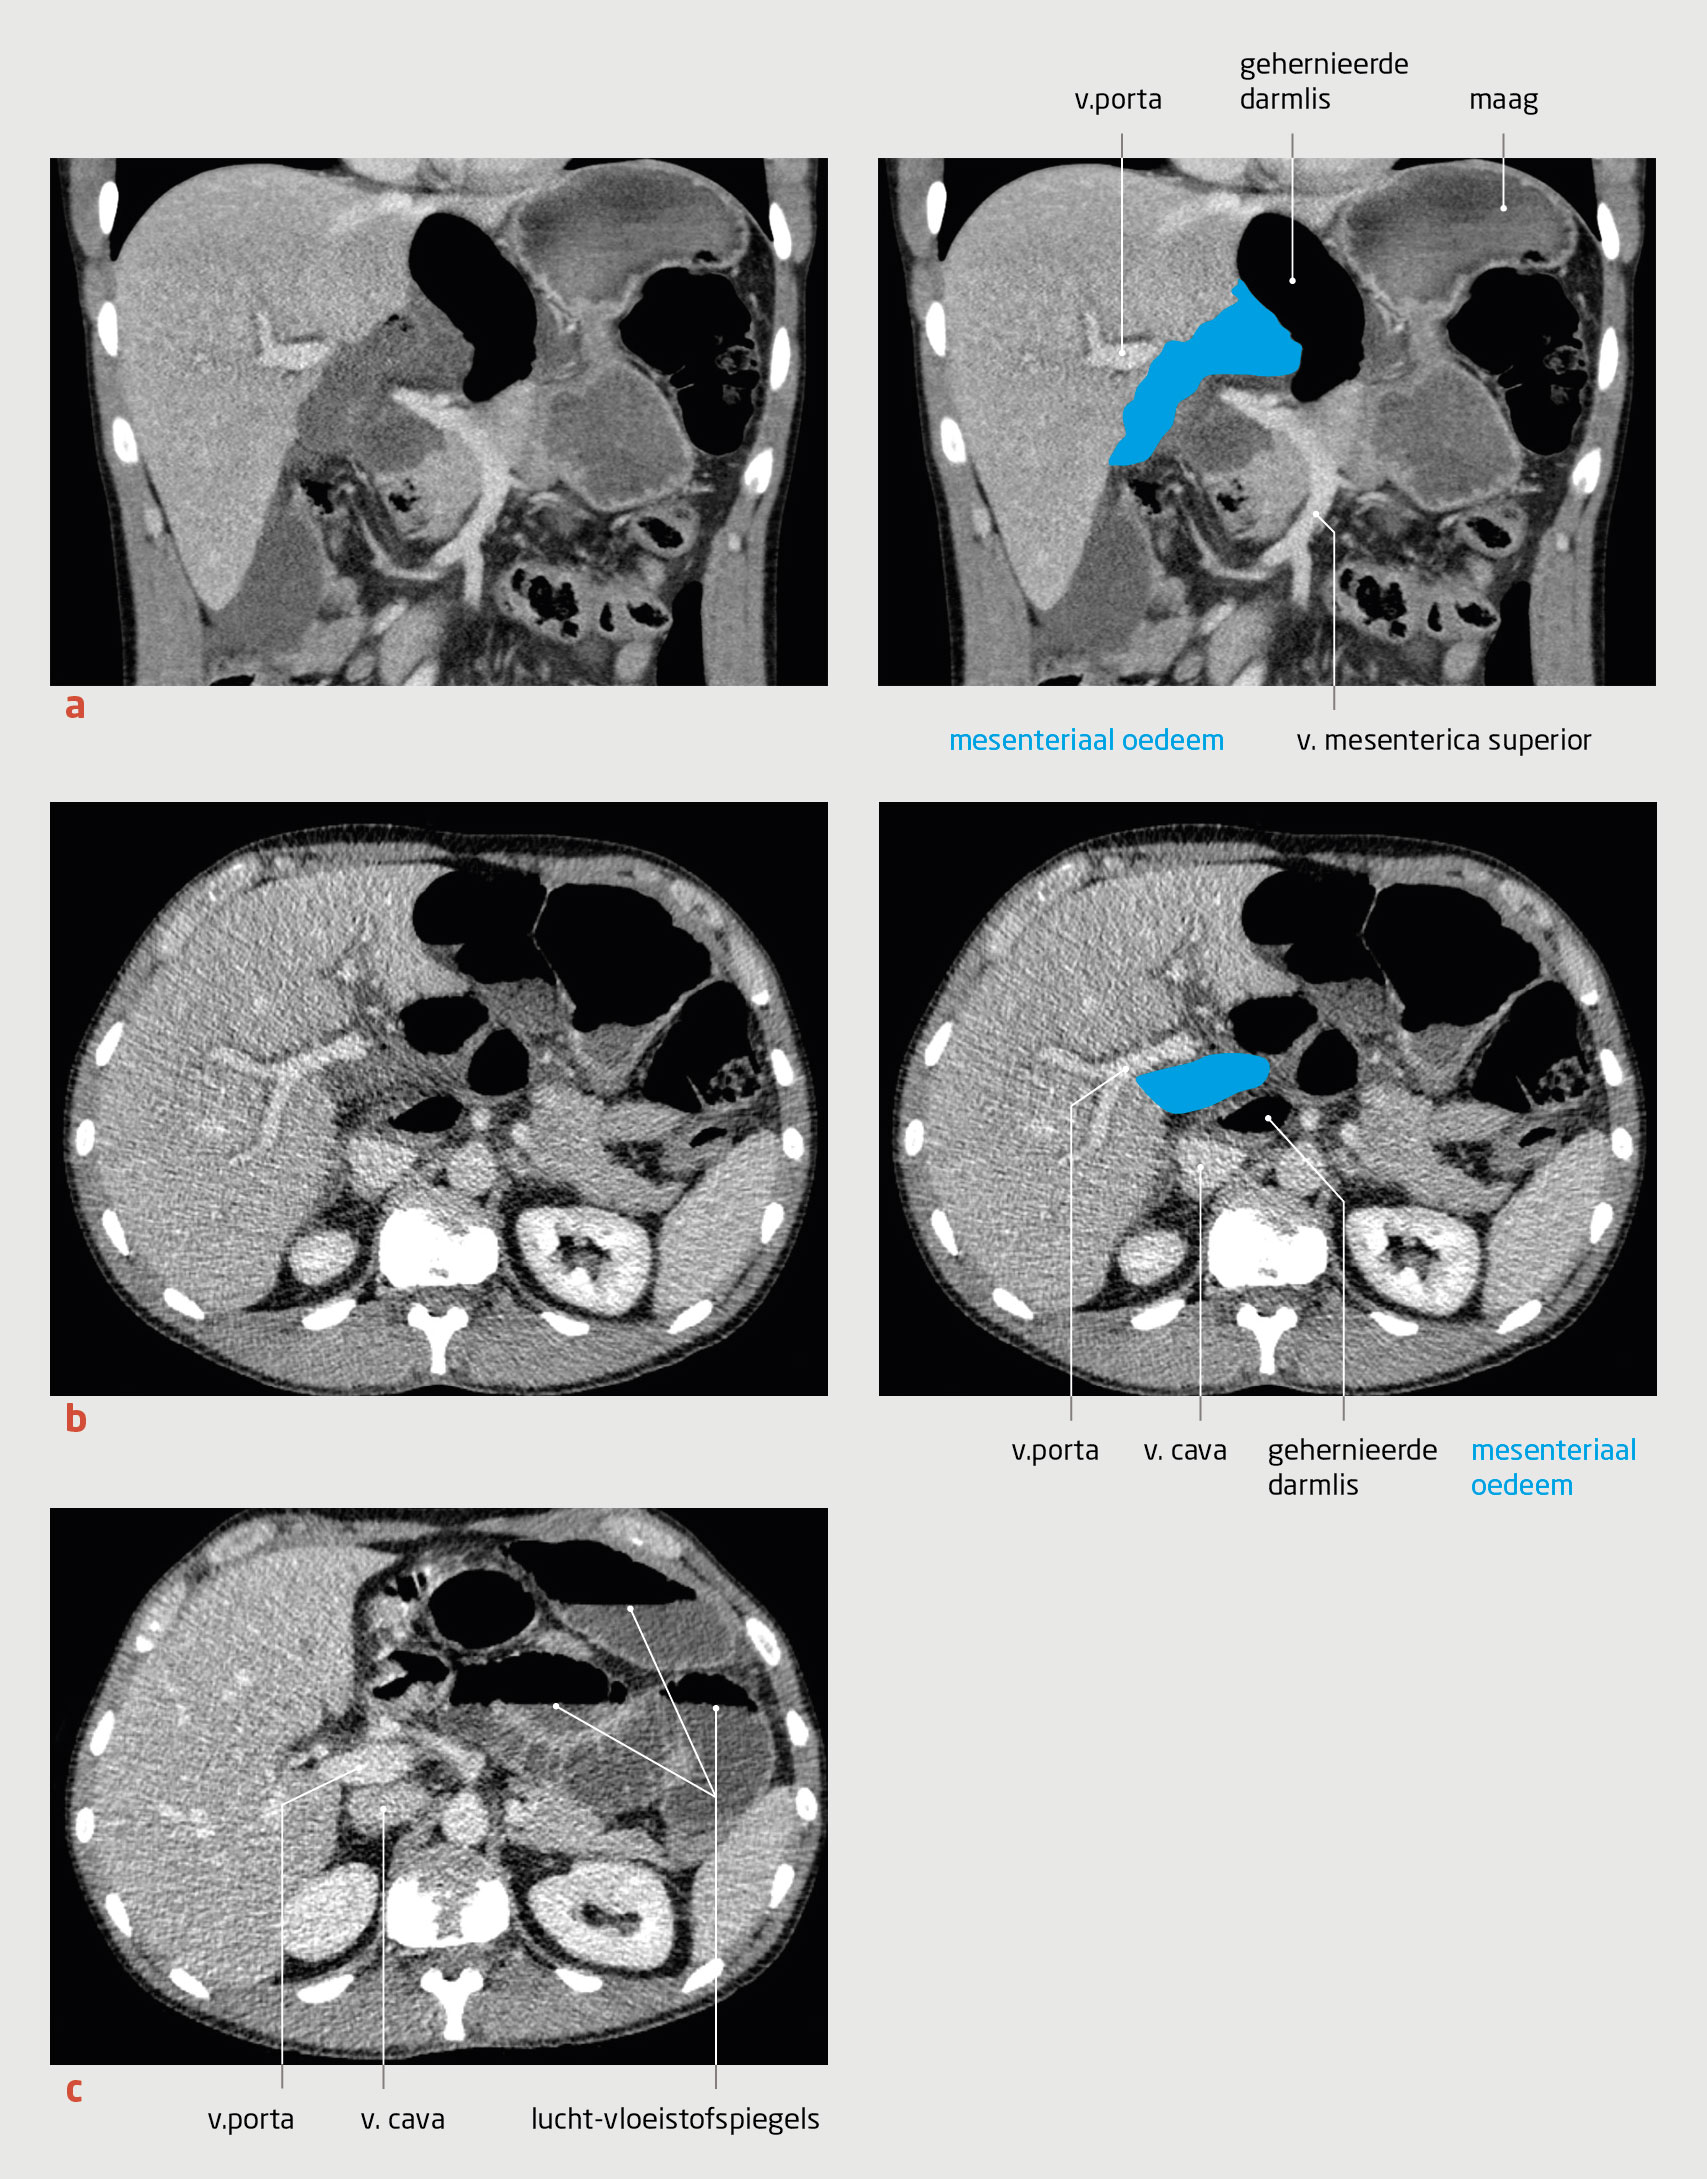

In de uren daarna bleef de patiënt pijn houden, ondanks pijnstilling met opiaten en scopolaminebutyl. Hoewel er geen afwijkingen waren in de vitale parameters, maakte de patiënt een toenemend zieke indruk, waardoor andere oorzaken van een acute buik waarschijnlijker werden. We besloten daarom niet langer te wachten met de CT van het abdomen en hierbij ook contrast te geven. Nu werd de diagnose duidelijk. De CT-scan liet namelijk een herniatie van de dunne darm door het foramen van Winslow zien, met tekenen van ischemie van het gehernieerde stuk darm (figuur 2a en 2b).

Figuur 2 | Herniatie van dunne darm door het foramen van Winslow

CT-scans met contrast van het abdomen van de patiënt met acute buikpijn. (a) Preoperatieve opname, coronale coupe; de dunnedarmlis is gehernieerd door het foramen van Winslow (foramen epiploicum) en ligt nu tussen de lever en de maag, met daarbij veel mesenteriaal oedeem. (b) Preoperatieve opname, axiale coupe; de gehernieerde darmlis ligt tussen de v. cava en de v. porta. Het mesenteriale oedeem is een teken van ischemie. (c) CT bij heropname, axiale coupe; de gedilateerde darmlissen met lucht-vloeistofspiegels wijzen op een ileusbeeld, maar de v. porta en v. cava liggen vlak naast elkaar. Er is dus geen recidief van herniatie door het foramen van Winslow.

Het is niet altijd even eenvoudig om de diagnose ‘inwendige herniatie’ op basis van CT te stellen. Vaak kan de diagnose pas worden gesteld als er tekenen van obstructie van de dunne darm zichtbaar zijn, zoals gedilateerde darmlissen, een verplaatste vaatsteel en verminderde aankleuring van de darmwand. Kenmerkend voor herniatie door het foramen van Winslow is de aanwezigheid van mesenterium tussen de v. cava inferior en de v. porta (zie figuur 2b).